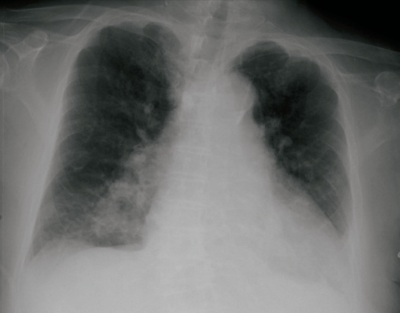

胸部エックス線写真を別に示す。血液検査では、TSH 160.5 μU/mL(基準 0.2~4.0)、FT₄ 0.04 ng/dL(基準 0.8~2.2)。